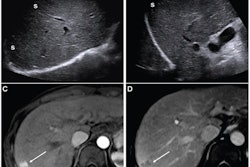

The team included patient records from 206 HCC patients who underwent a liver transplant from 2011 to 2017. Two readers blinded to the original report reviewed immediate pretransplant imaging within 90 days and characterized observations according to the LI-RADS algorithm.

Using this, tumors were categorized into the following: viable (LI-RADS 4, 5, or treatment response), equivocal (LI-RADS 3 or treatment response), and no viable disease (only LI-RADS treatment response). Meanwhile, the patients were designated as within or outside the Milan criteria for liver transplantation. The team compared these per-patient designations with the presence of viable disease at explant pathology.

The researchers found that per-patient assessment of pretransplant imaging had an NPV of 32% and 26% for both readers in predicting viable disease.

They also reported that 75% (reader 1) and 77% (reader 2) of patients found to have had equivocal status had residual tumors at explant pathology. Finally, the team found that the weighted interreader reliability was marked (κ = 0.62).